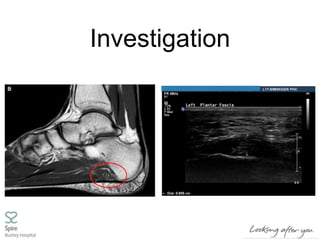

Investigation

• Clinical assessment - include XRs,

USS to define pathology and PF

thickness, r/o other pathology